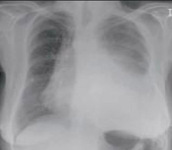

Chest x-ray showing early ill-defined opacities of the right upper lobe above the minor fissure consistent with early changes of aspiration pneumonia

From the personal collection of Dr R. Kanner, University of Utah School of Medicine